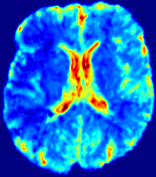

LesionRefer to captionRefer to captionRefer to captionRefer to captionRefer to captionRefer to caption𝐕rgbsubscript𝐕𝑟𝑔𝑏{\bf{V}}_{rgb}Refer to captionRefer to captionRefer to captionRefer to captionRefer to captionRefer to caption𝐕2subscriptnorm𝐕2{\|\bf{V}}\|_{2}Refer to captionRefer to captionRefer to captionRefer to captionRefer to captionRefer to captionRefer to caption3.53.53.52.82.82.82.12.12.11.41.41.40.70.70.70.00.00.0(mm/s)𝑚𝑚𝑠(mm/s)D𝐷DRefer to captionRefer to captionRefer to captionRefer to captionRefer to captionRefer to captionRefer to caption0.0200.0200.0200.0160.0160.0160.0120.0120.0120.0080.0080.0080.0040.0040.0040.0000.0000.000(mm2/s)𝑚superscript𝑚2𝑠(mm^{2}/s)Slice #1Slice #2Slice #3Slice #4Slice #5Slice #6

Figure 4: PIANO feature maps for another patient in the ISLES 2017 training set, where the lesion is located in the right hemisphere. Top row: segmented stroke lesion region (white) on different slices. The corresponding slices for the PIANO feature maps are shown in the following rows.

For a better insight into an estimated velocity field 𝐕𝐕{\bf{V}} and diffusion field 𝐃𝐃{\bf{D}}, we compute the following maps: (1) 𝐕rgbsubscript𝐕𝑟𝑔𝑏{\bf{V}}_{rgb}: Color-coded orientation map of 𝐕=(Vx,Vy,Vz)T𝐕superscriptsuperscript𝑉𝑥superscript𝑉𝑦superscript𝑉𝑧𝑇{\bf{V}}=(V^{x},V^{y},V^{z})^{T}, obtained by normalizing 𝐕𝐕{\bf{V}} to unit length and mapping its 3 components to red, green, blue respectively; (2) 𝐕2subscriptnorm𝐕2\|{\bf{V}}\|_{2}: 222 norm of 𝐕𝐕{\bf{V}}; (3) D𝐷D: scalar field in Eq. 5.

Fig. 3 and Fig. 4 show the PIANO feature maps estimated from two ISLES 2017 patients: all are highly consistent with the lesion in both cases. Details of the blood flow trajectories are revealed in 𝐕rgbsubscript𝐕𝑟𝑔𝑏{\bf{V}}_{rgb} by the ridged patterns and the sharp changes of colors in the unaffected (right) hemisphere, while the flat patterns appearing within the lesion provide little directional information about the velocity and indicate low velocity magnitudes. Velocity magnitudes are more directly visualized via 𝐕2subscriptnorm𝐕2\|{\bf{V}}\|_{2}, from which one can easily locate the lesion where 𝐕2subscriptnorm𝐕2\|{\bf{V}}\|_{2} is low. D𝐷D also indicates lower diffusion values in the lesion, though with less contrast potentially due to the fact that it captures the accumulated effect of CA diffusion at the voxel-level.